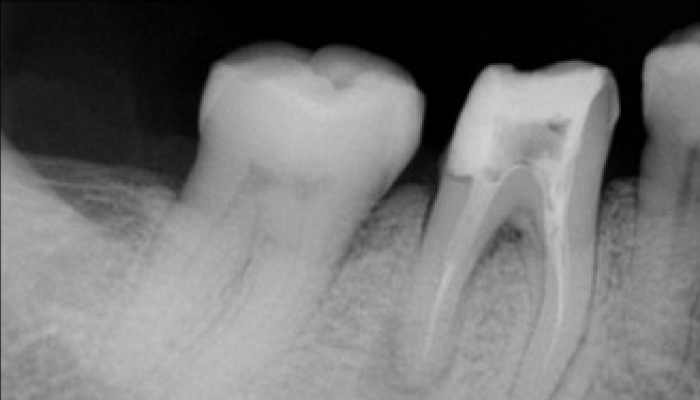

충치치료 전후 사례

• 치료 전

치료 후

• 치료전

치료후